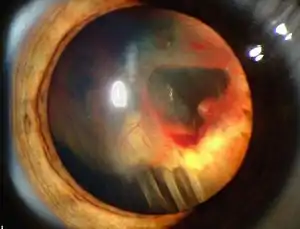

| Slit lamp photograph showing retinal detachment beneath blood inside the eye. | |